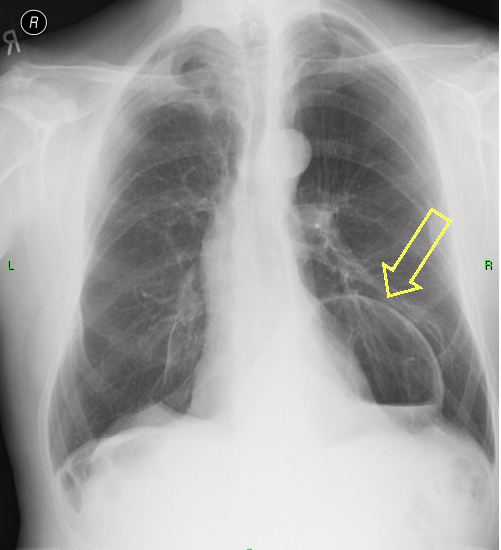

18. Tuberculosis a.) CT, b.) PA radiograph

45 year old man, pulmonary TB proven by microbiological culture.

LLL on CT: irregular, multicavitary nodular lesion: caverna.

(by the contribution of Zsuzsanna Monostori, MD, PhD)